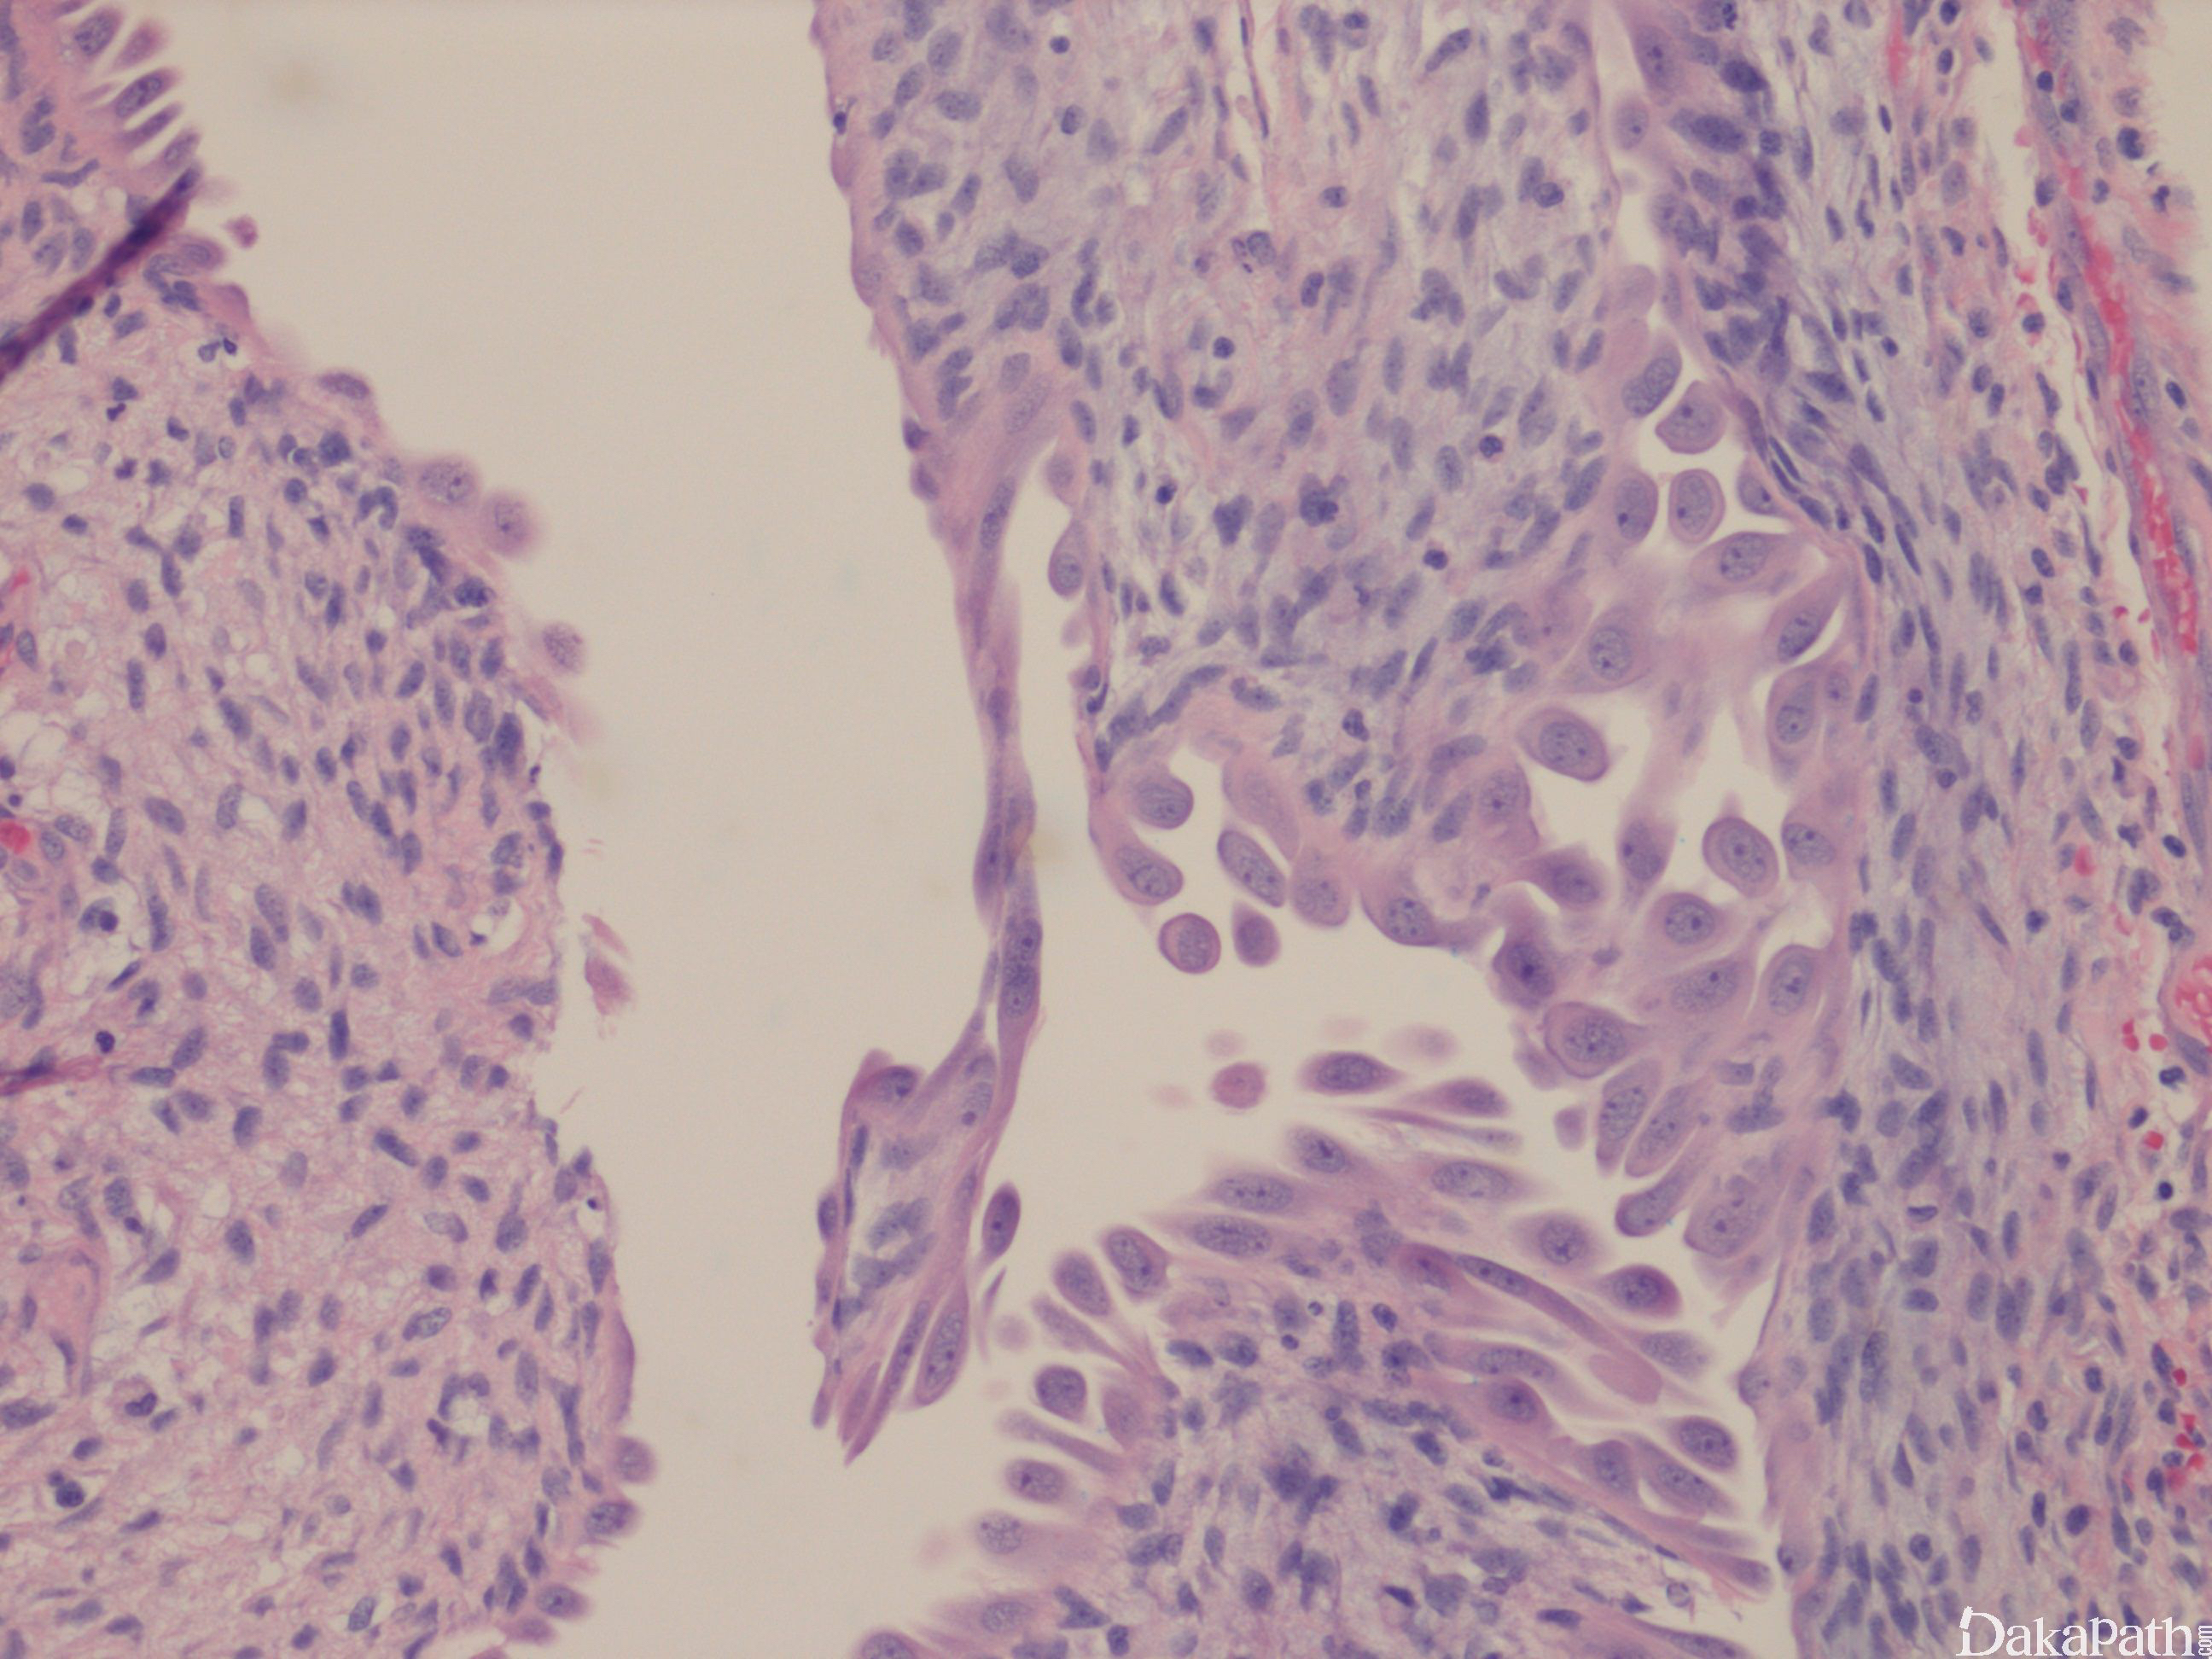

囊肿内衬扁平、立方或鞋钉样上皮细胞,或上皮脱落;

间质由纤维组织构成,可见波浪形、绳索样胶原,常见较多炎症细胞浸润,可伴局灶细胞致密区及分化成熟的小管;